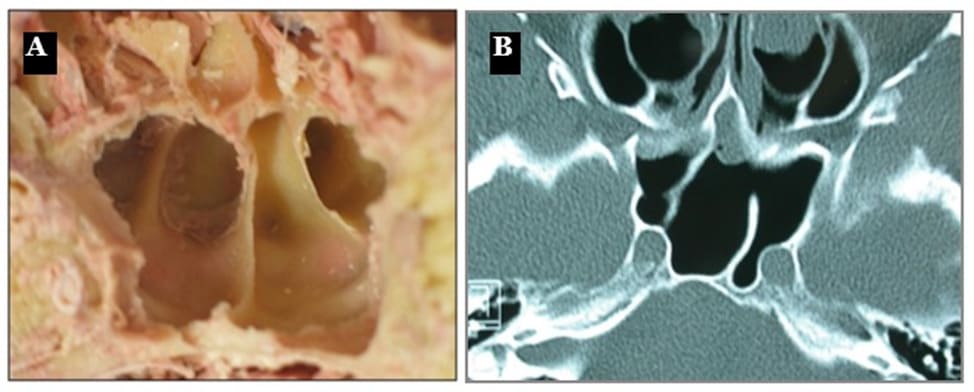

Generally, the sphenoid sinuses are separated by at least one intersinus septum. This septum is a thin sagittal bony plate, rarely median, which should always be identified on preoperative imaging. Indeed, it might be inserted onto the carotid or the optic nerve canal instead of the sellar floor. Some sphenoid sinuses have no intersinus septum, others have an accessory septum or even multiple ones (6).

Figure 3: (A) Coronal cadaver view of the sphenoid sinuses. (B) Axial CT-scan demonstrating an oblique paramedian intersinus septum and a bony partition in the left sphenoid sinus.